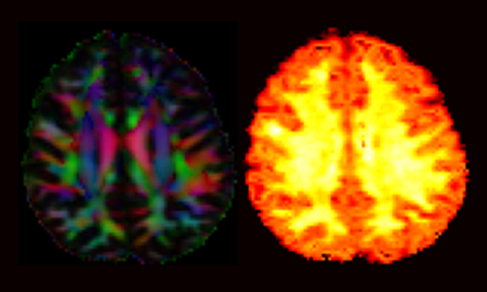

Die MR Gruppe beschäftigt sich in erster Linie mit der Entwicklung von neuen Methoden auf dem Gebiet der Magnetresonanztomographie (MRT) und den hierzu benötigten Messsequenzen. Der Schwerpunkt unserer Forschung liegt in der Hirnforschung. Insbesondere interessieren uns die Quantifizierung der MR Daten, die strukturelle und funktionelle Bildgebung, Bildgebung von Natrium sowie der Bereich der Hochfeld MR.

Unterstützt werden diese Aktivitäten durch die Konstruktion und Implementierung neuer Hardware. Ein weiterer Forschungsschwerpunkt ist die Kombination von MRT und Positronen-Emissions-Tomographie (PET) in einem kombinierten MR-PET Gerät. Die Kombination eröffnet einzigartige Möglichkeiten zur Erforschung und Anwendung neuer Methoden der grundlagenorientierten und translatorischen Hirnforschung.

- Diffusions-Bildgebung